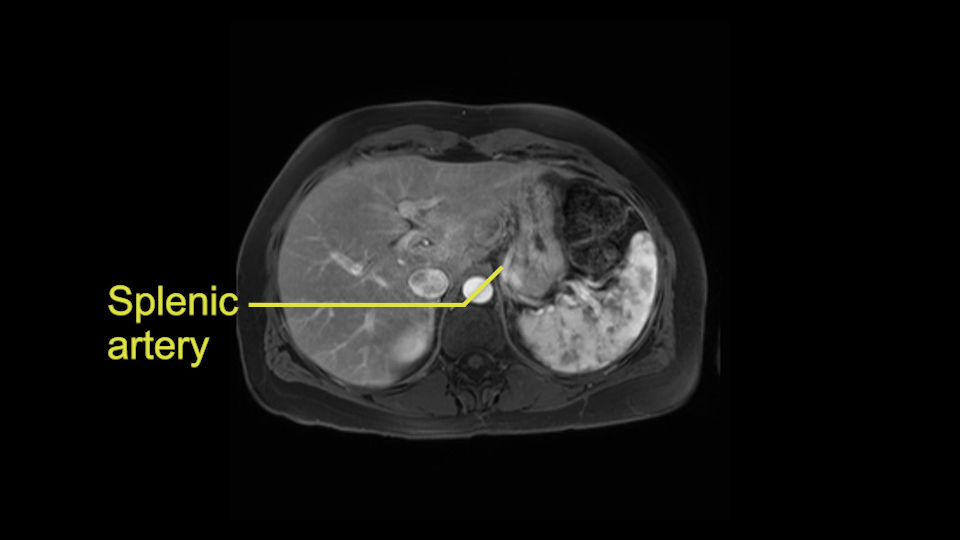

The second slowing down moment or consideration I give to a distal pancreatectomy is the anatomy of the portal vein and the splenic artery. And so I look here and the anatomy is pretty straightforward. The splenic vein comes off normally and runs behind the pancreas and I can see the artery superior to that, again coming off in a normal manner from the celiac axis. So those two things, the portal vein and the splenic artery will be taken normally in this procedure.

I think the splenic vein, once I have slowly teased it off from the cyst and from the retropancreatic parenchyma, I would put a vessel loop around it to serve as a traction. So once you have the vessel loop or probably umbilical tape, to retract or pull the pancreatic parenchyma while we slowly tease it off and try to move superiorly to be able to expose the splenic artery. That is again another slow-down moment because sometimes we think that it is the splenic artery at the superior edge of the pancreas, but it could also be the hepatic artery as it branches from the celiac artery.

Other slowing down moments with this procedure include dissection of the splenic vein and splenic artery. These are technically challenging moments and important moments where care needs to be taken. Not only to avoid bleeding and injury to the vessels but also to ensure an adequate margin.